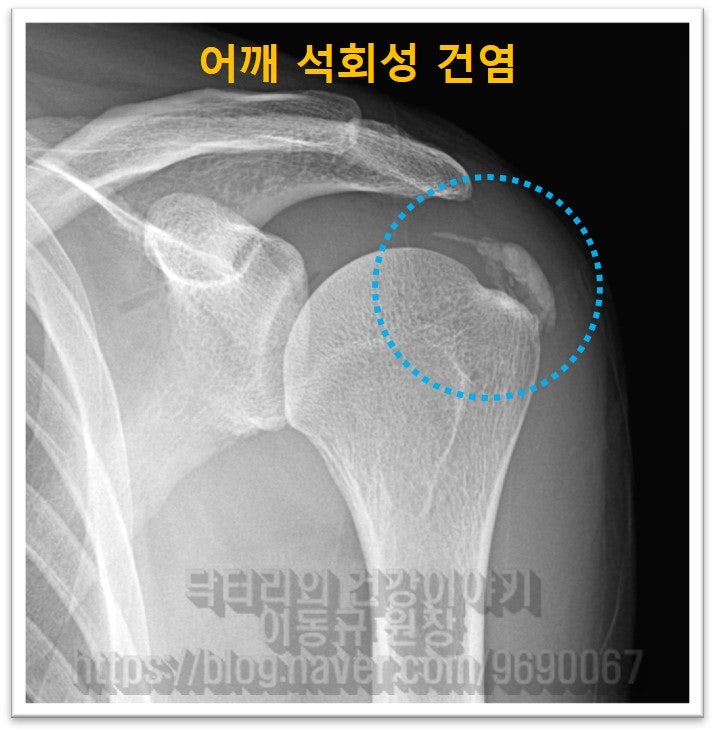

어깨 석회성 건염 또한 비수술적으로 충분히 치료 할 수 있습니다. 제가 하고 있는 뉴핌스치료(석회분쇄흡입술) 는 어깨 석회성 건염을 비수술적으로 석회를 제거하는 시술입니다. 이번에 보여드릴 케이스는 부산에서 오신 환자분 입니다. 부산에서 어깨 통증이 너무너무 심해서 병원을 가니 석회가 너무 커서 수술을 해야 한다고 이야기를 들었다고 합니다. 환자분은 사업을 하시는 분인데 수술할 여건이 도저히 되지 않아 비수술적 방법을 찾다 저한테 오셨다고.. 우선 사진을 살펴보도록 하겠습니다.

이렇게 상당히 큰 석회라도 충분히 비수술적 치료를 할 수 있습니다. 그래서 뉴핌스치료(석회분쇄흡입술)를 시행하였습니다.